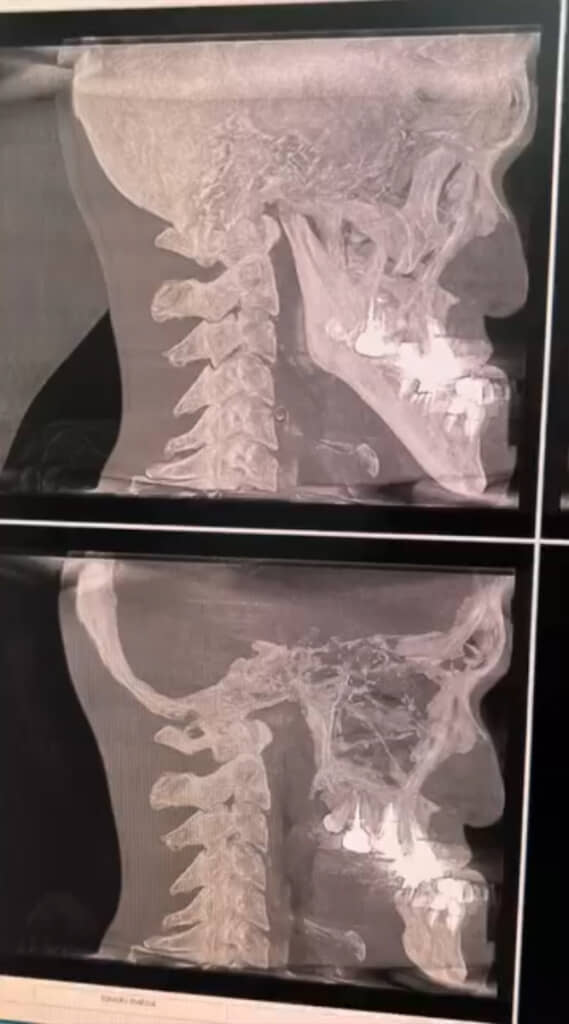

当時話題になったのは、視聴者からの「アゴのレントゲンがみたい」というリクエストに応える形で、城之内さんが実際に歯科医院に行って撮ってもらったときの動画です。自身のレントゲン写真に驚いた城之内さんが先生に「こんな長いのって、あんまりないですもんね」と聞いてみると、すぐに「ないです」との言葉が返ってきました。

さらに、いわゆるエラ(下顎角)のカドから下が特に長いことに衝撃を受けていると、先生から続けて「角度も……」と指摘され、城之内さんの顎が唯一無二であることが分かる結果となったのでした。

ここまで顎が伸びた原因については、先生いわく「遺伝的要素が一番多い」とのこと。しかし、親族は城之内さん以外は顎が長くないのだとか。また「カルシウムのとりすぎとかは……?」とも聞いてみましたが、先生は「牛乳などの栄養素が顎だけにいくのはありえない」と回答。結局、理由は謎のままとなりました。